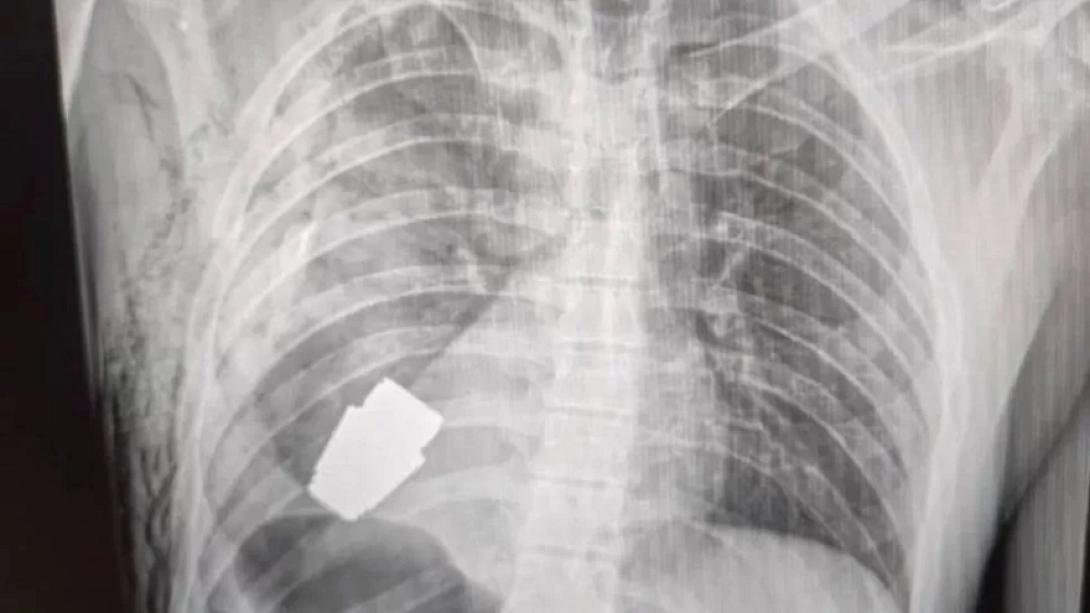

Μία νέα μελέτη κατέληξε στο συμπέρασμα πως πλέον η τεχνητή νοημοσύνη μπορεί να αναλύσει ακτινογραφίες και να διαγνώσει ασθένειες το ίδιο καλά με τους γιατρούς. Το software, το οποίο ονομάζεται X-Raydar, εκπαιδεύτηκε χρησιμοποιώντας ακτινογραφίες από 1.8 εκατομμύριο ασθενείς και ψάχνει για 37 πιθανές ασθένειες. Στις 35 από τις 37 ασθένειες ήταν το ίδιο ή περισσότερο ακριβής από την ανάλυση των γιατρών.

Η AI μπορεί να μειώσει το φόρτο εργασίας των γιατρών και τυχόν καθυστερήσεις στις διαγνώσεις, προσφέροντας στους ακτινολόγους “την απόλυτη δεύτερη γνώμη”, ενώ είναι απαλλαγμένη από το ανθρώπινο λάθος ή την προκατάληψη.

Το software αντιλαμβάνεται πως μερικές ανωμαλίες στην ακτινογραφία είναι πιο σοβαρές από άλλες και μπορεί να ειδοποιήσει τους γιατρούς για τις πιο επείγουσες περιπτώσεις. Για να ελεγχθεί η ακρίβεια των αποτελεσμάτων, περισσότερες από 1.400 ακτινογραφίες ελέγχθηκαν από έμπειρους ακτινολόγους.

''Αν ένας ασθενής που έχει ένα γνωστό καρδιολογικό πρόβλημα χρειαστεί μία ακτινογραφία, οι γιατροί αναπόφευκτα θα επικεντρωθούν στην καρδιά αντί για τα πνευμόνια για παράδειγμα. Αυτό είναι απόλυτα κατανοητό, αλλά έχει το ρίσκο να μην ανιχνευθούν προβλήματα σε άλλες περιοχές.΄΄τόνισε μέλος της Ερευνητικής ομάδας.

Οι ερευνητές αποκαλούν το X-Raydar το “μέλλον της ιατρικής” και πιστεύουν πως θα χρησιμεύσει ως ένας πολύτιμος συνεργάτης για πολυάσχολους γιατρούς. Το software είναι διαθέσιμο ως open source για μη εμπορική χρήση, για να μπορέσει να επιταχυνθεί η ανάπτυξη της έρευνας.